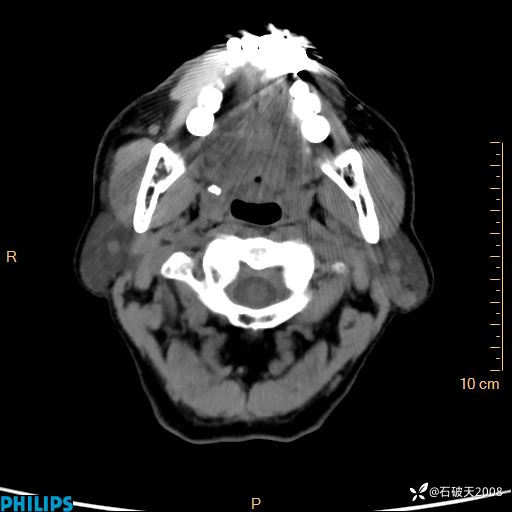

静脉期